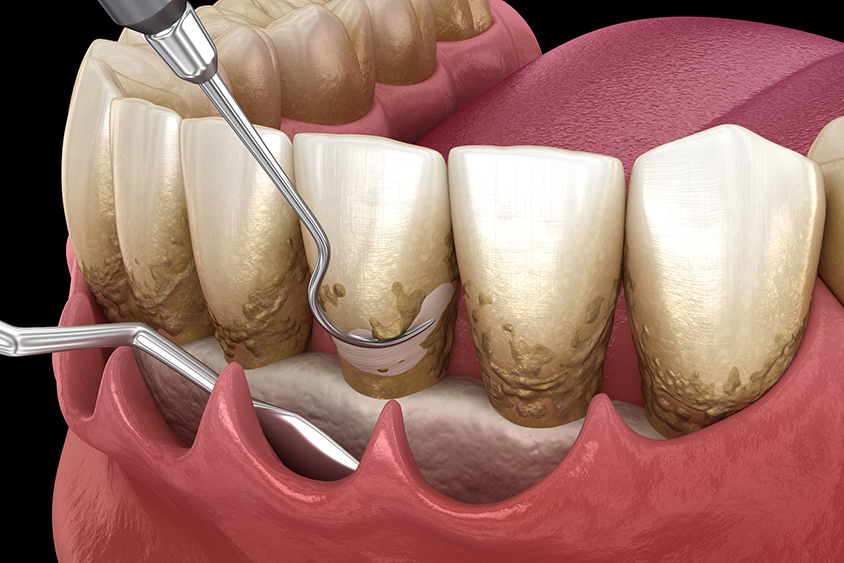

そもそも歯周病治療では、プラーク(歯垢)や歯石など、歯周病の原因となる汚れをしっかり除去することが重要です。しかし重症になると、そのままでは見えない歯の根っこの先までプラークや歯石が付着してしまいます。そうした歯茎の奥深くにある汚れを除去するため、「フラップ手術」と呼ばれる外科手術を行います。

フラップ手術

フラップ手術では、まず歯茎を切開して歯の根っこまで見えるようにし、根っこの先までこびりついた汚れを目視で確認します。その上で、歯周病の原因となるプラークや歯石をすみずみまで除去。歯周病菌を取り残さないようにします。